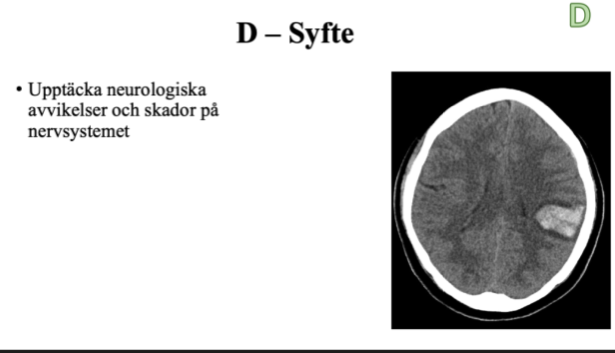

D

- vad är syftet på D?

A

T.ex. förhöjt intrakraniellt tryck, stroke

Q